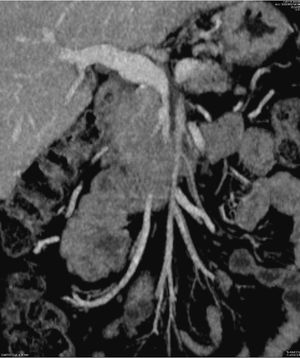

Técnica quirúrgica (vídeo cirugía)El uso de shunt íleo-cava transitorio se indicó en un paciente de 45 años afecto de adenocarcinoma de páncreas localmente avanzado que condicionaba una severa colateralidad venosa, con mutación BRCA2; tras recibir 11 ciclos de neoadyuvancia con esquema FOLFIRINOX, con buena tolerancia. Finalizado este, se realizó estudio mediante tomografía computarizada (TC) toraco-abdominal, PET/TC, y resonancia magnética nuclear (RNM), descartando afectación a distancia. Tras presentar el caso en comité multidisciplinario se planificó la intervención con ayuda de estudio 3D13 (figs. 1, 2, 3 y 4)(https://www.cellams.com). En el estudio preoperatorio se evidenció lesión pancreática con afectación del confluente venoso EMP con extensión hasta la confluencia de dos venas ileales (Vil1 y Vil2) y yeyunal (VYy), y contacto con la arteria mesentérica superior (AMS). La afectación de toda la extensión de la vena mesentérica superior (VMS) comportaba la imposibilidad de la anastomosis con seguridad.

Estudio 3D preoperatorio13. Se evidencia la oclusión del eje esplenoportomesentérico y abutment de la arteria mesentérica superior por el tumor.

SMA: arteria mesentérica superior; CHA: arteria hepática común; PHA: arteria hepática propia; GDA: arteria gastroduodenal; SA: arteria esplénica; PV: vena porta; SV: vena esplénica; VIL: vena ileal; VIL1: vena ileal tributaria 1; VIL2: vena ileal tributaria 2; VYY: vena yeyunal; IMV: vena mesentérica inferior; MSC: mesocolon.

En amarillo se señala el tumor pancreático.

Detalle de la vascularización venosa del estudio 3D13.